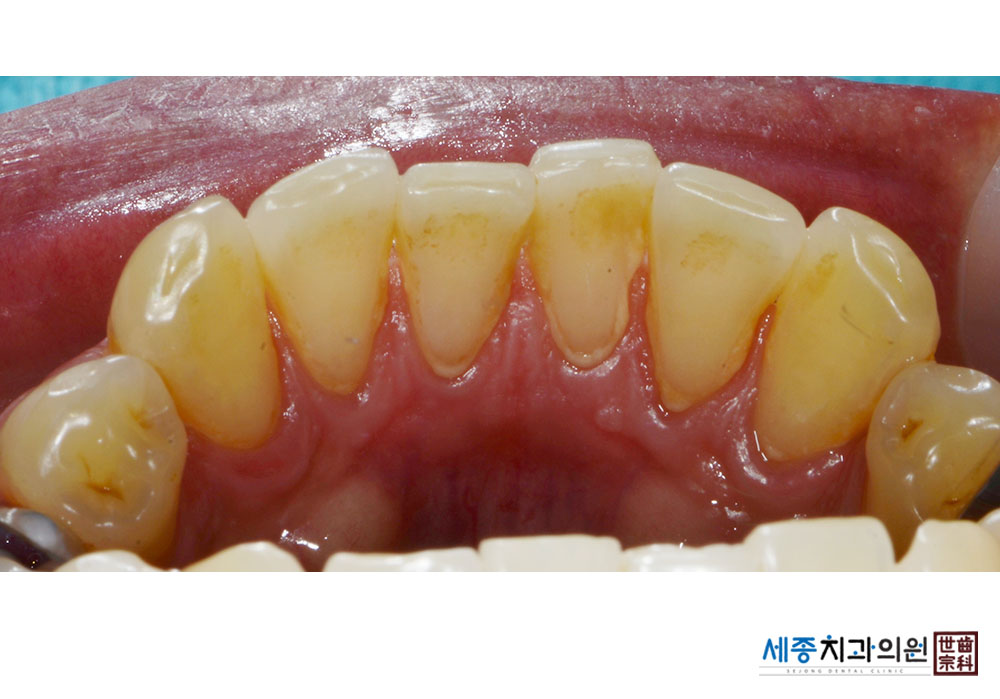

[스케일링] 치주질환 예방 스케일링

치료전 : 2019-11-05

치료후 : 2019-11-05

가글마취&저주파 스켈러를 사용한 스케일링